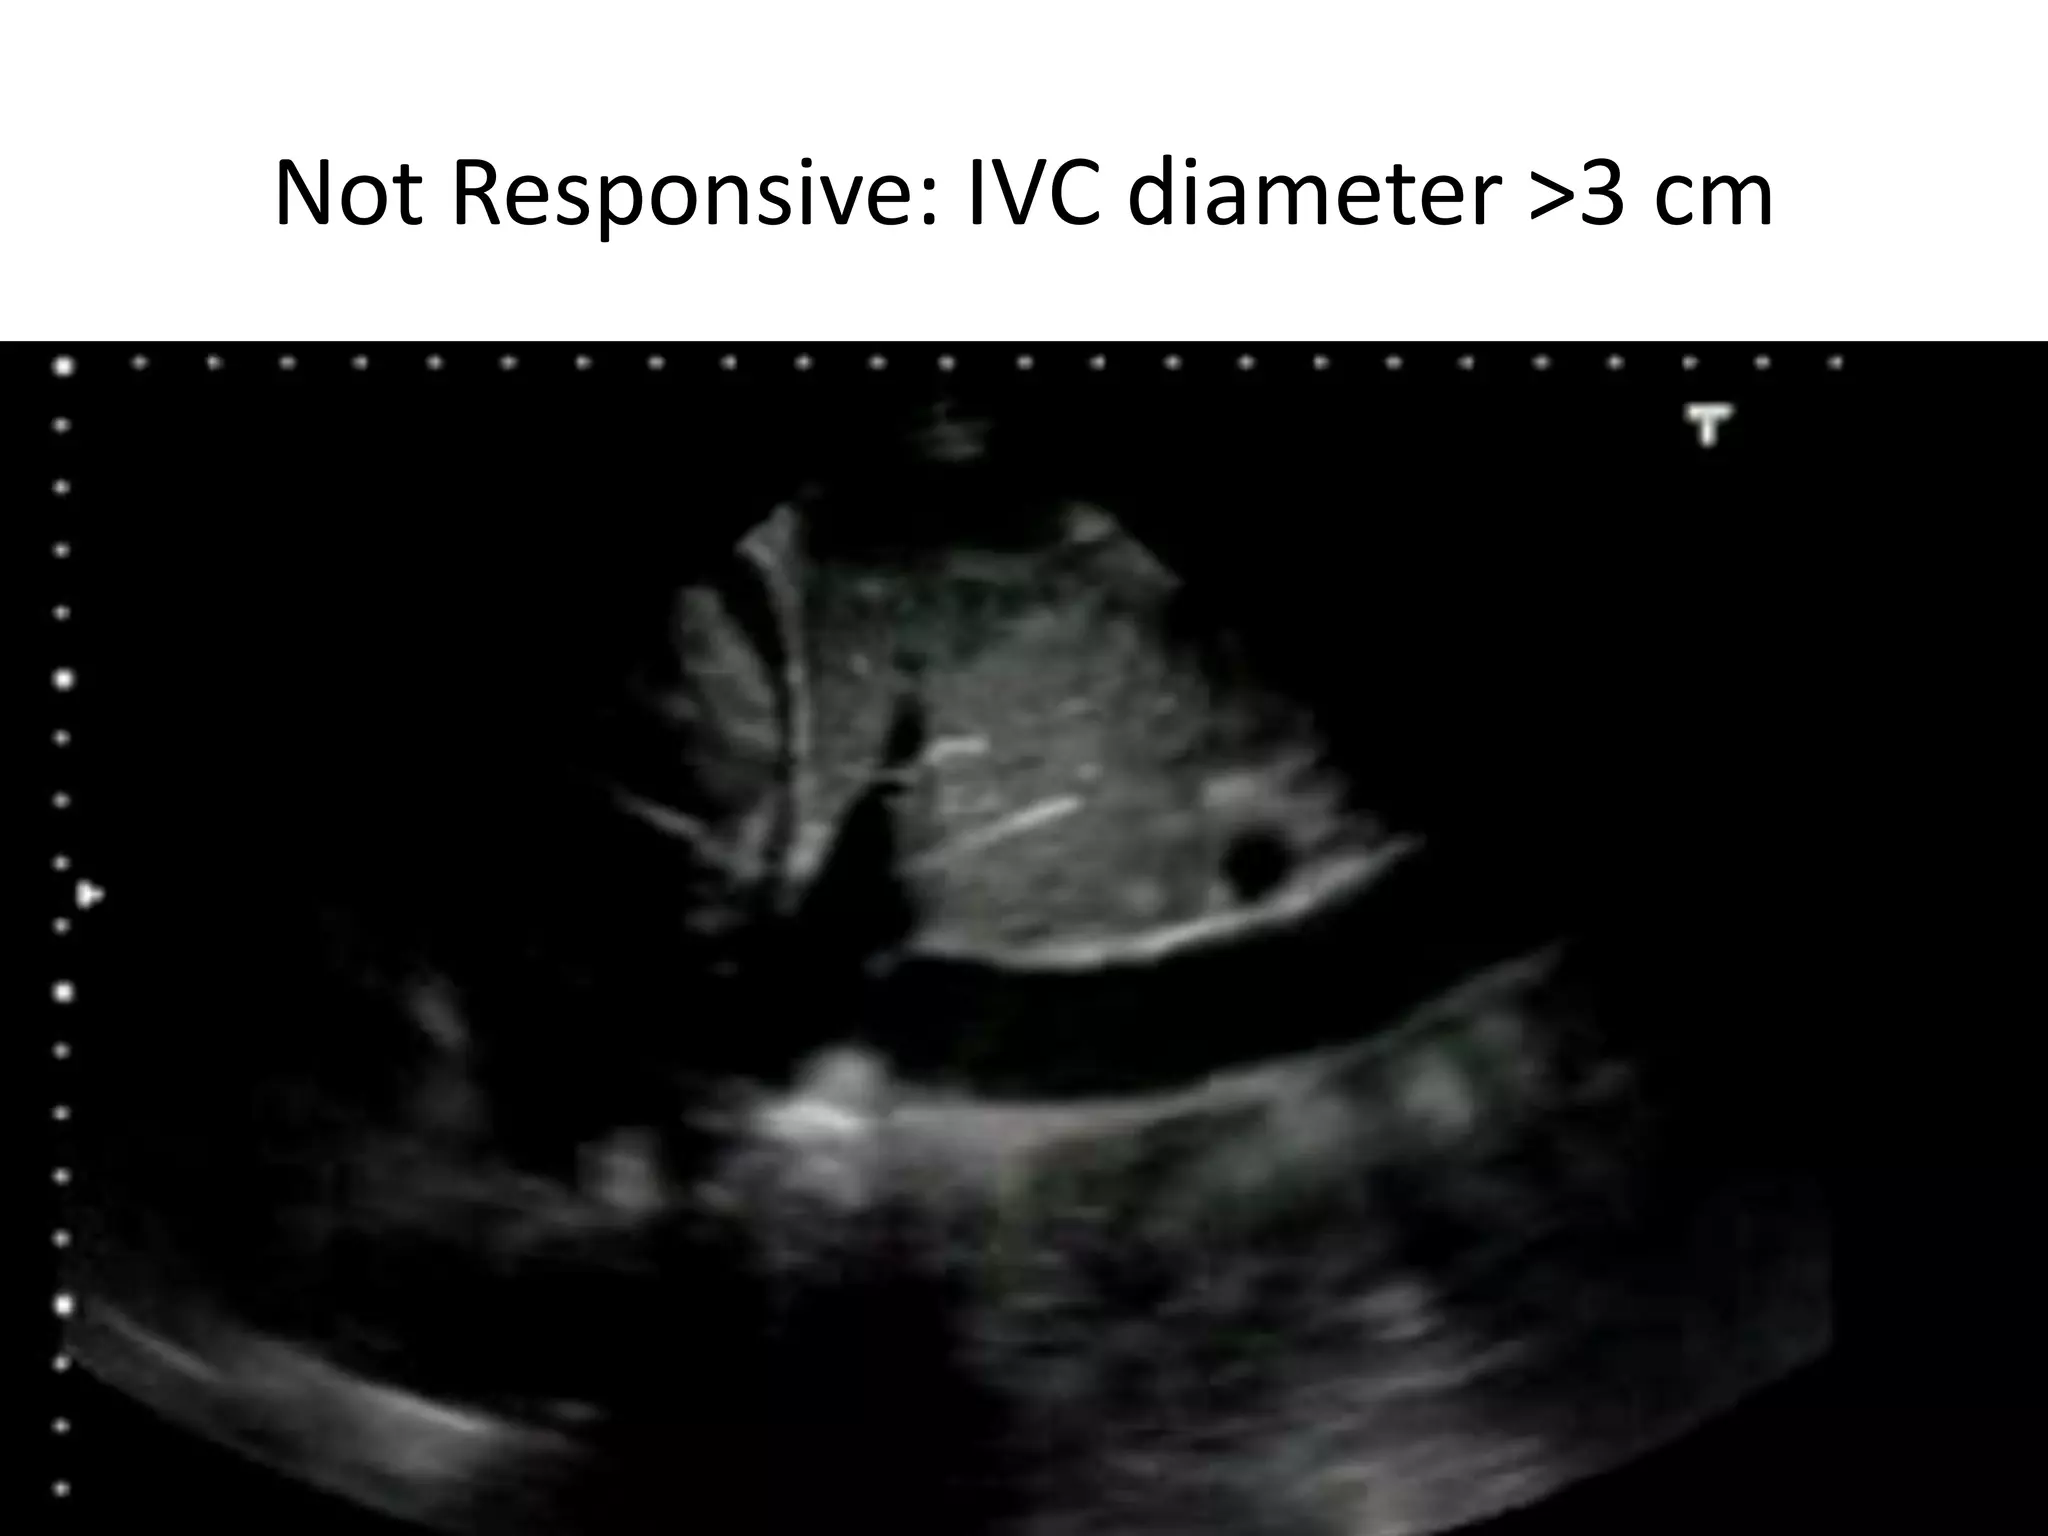

Not Responsive: IVC diameter >3 cm

Bassel Ericsoussi, MD

Not Responsive: IVCdiameter >3 cm Bassel Ericsoussi, MD 19